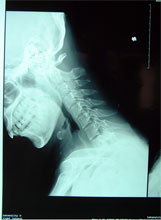

寰枢关节不稳脱位         高位颈脊髓受压迫,瘫痪呼吸困难